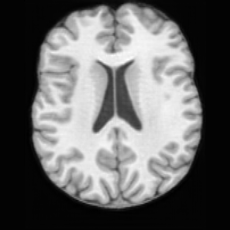

Unconditional Generation. Fig. 4 (a) presents examples of paired lesion masks and brain images generated by USB. Notably, although the paired lesion-brain generation begins unconditionally from random noise, USB produces lesion masks exhibiting diverse locations, sizes, and shapes, while simultaneously generating anatomically coherent brain images with embedded pathological patterns that spatially correspond to the generated lesions within each pair.

In Tab. 1, we present the first quantitative benchmark evaluation of both generation tasks. For the unconditional generation task, we generated 256 paired lesion–brain samples for each lesion type (stroke and WMH). For the conditional generation task, we used masks from the ATLAS and ISLES test sets as stroke lesions, and masks from the ADNI test set as WMH lesions. Notably, for each lesion type, the unconditional generation achieved superior quantitative performance, highlighting that the paired diffusion mechanism effectively generates coherent lesion-brain pairs through joint modeling between USBbrain and USBlesion. Additional generation results are provided in Suppl. A.